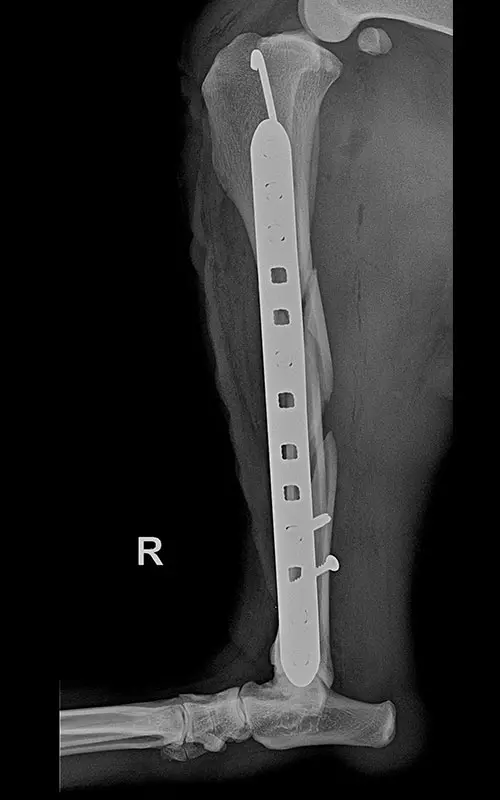

It is a common case where long tubular bones suffer multiple fractures and there is no bone lying on top of each other after repositioning that would aid in stability after fixation. The K-wire-and-plate combination already known during DCP plating can also be used for locking plating:

- Among locking systems, only the polyaxial system is fully suitable for this task, because during the insertion of srews the medullary nail can be bypassed (cf. in monoaxial systems, if the nail is under the plate hole, no screw can be inserted in that hole).

In our case, a 10-year-old labrador is involved in a car accident and his left femur and right tibia are severely injured. The dog had difficulty moving anyway due to severe hip arthrosis. During one surgical narcosis, K-pin - polyaxial locking plating was applied to both bones, the larger fragments were also fixed with 1-1 lag screws.